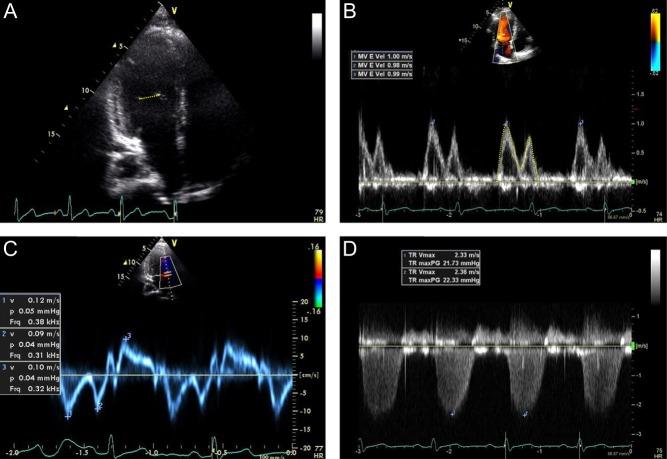

A total of 467 adults without cardiopulmonary disease and normal exercise capacity (age range: 18-85 years) underwent symptom-limited treadmill exercise testing with Doppler measurement of rest and exercise pulmonary artery systolic pressure.

There was a progressive increase in rest and exercise pulmonary artery pressures with increasing age. Pulmonary artery systolic pressures at rest and with exercise were 25±5mmHg and 33±9mmHg, respectively, in those <40 years, and 30±5mmHg and 41±12mmHg, respectively, in those ≥70 years. While elevated left-sided cardiac filling pressures were excluded by protocol design, markers of arterial stiffness associated with the age-dependent effects on pulmonary pressures.